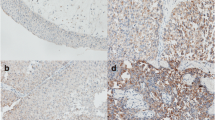

To obtain the expression pattern of CXCL10 in BLCA, we conducted a comprehensive expression analysis that incorporated different clinical variables from TCGA-BLCA cohort. It was observed that CXCL10 was significantly upregulated in tumor tissues (Fig. 1A; p = 0.003). Upregulation of CXCL10 expression was also observed in non-papillary tumors (Fig. 1D; p = 7.2e−08) and in higher grades (Fig. 1E; p = 5e−05). However, no statistically significant differences were observed with regards to gender (Fig. 1B, p = 0.46), age (Fig. 1C, p = 0.5), or T (Fig. 1F; p = 0.95), N (Fig. 1G; p = 0.73), and M staging (Fig. 1H, p = 0.51). Furthermore, we examined the impact of CXCL10 on the prognosis of BLCA patients. Analysis of TCGA-BLCA, Imvigor210, and GSE70691 datasets revealed that the survival analysis of CXCL10 in BLCA showed statistically significant differences (Figs. 2A–C) (log-rank test, p < 0.05), suggesting that patients with high CXCL10 expression may have a better prognosis.

In addition, we verified the expression of CXCL10 in different human bladder cancer cells by qRT‑PCR. The findings revealed a significant upregulation of CXCL10 in a variety of bladder cancer cells, including sw780, T24, 5637, RT4, and RT112, compared with normal bladder cell(Sv-huc) (Fig. 1I, all p < 0.05 Table 1).